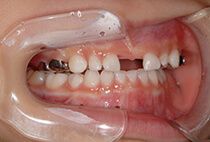

出っ歯を目立たずしっかり治したい。とのご希望、ビジネスシーンでも目立たないインビザラインを選択なさいました。30代男性の症例です。

治療計画は

抜歯した上顎も親知らずまできれいに並べたことで、上下ともに14本ずつ=非抜歯と同じ28本の歯列が完成しました。

治療から2年後も+ホワイトニングできれいな歯並びを保っています。

出っ歯が気になる

上顎前突、過蓋咬合

30代男性

3.5年

36回

唇側矯正、圧下用インプラントアンカー

矯正:1,270,500円+毎月調整量:6,050円

上顎2本抜歯して前歯を下げます。

奥歯のかみ合わせを治します。

インプラントアンカーを使用して前歯をしっかりコントロール、

過蓋咬合(かみ合わせの深さ)を改善しました。

治療前

治療後